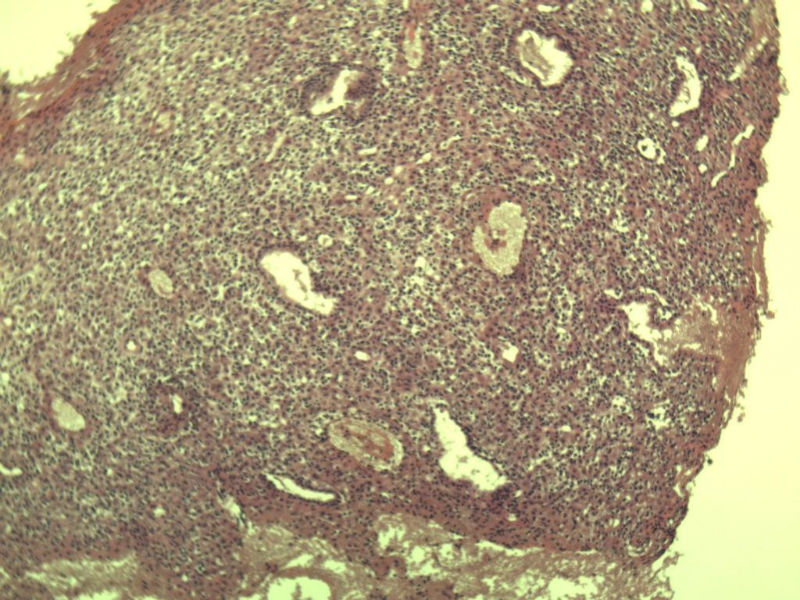

这是另外一个 40岁 经期延长 流血量增多 半年 这是蜕膜样变吧 有什么意义吗? 要报告不?